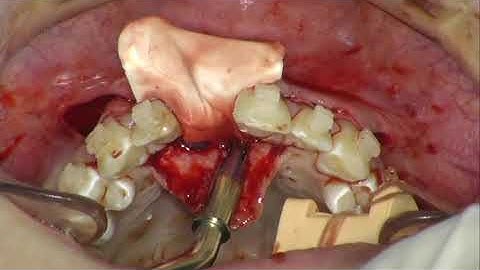

Dr. Robert Carvalho da Silva: Vertical ridge augmentation using a titanium-reinforced dPTFE memb...